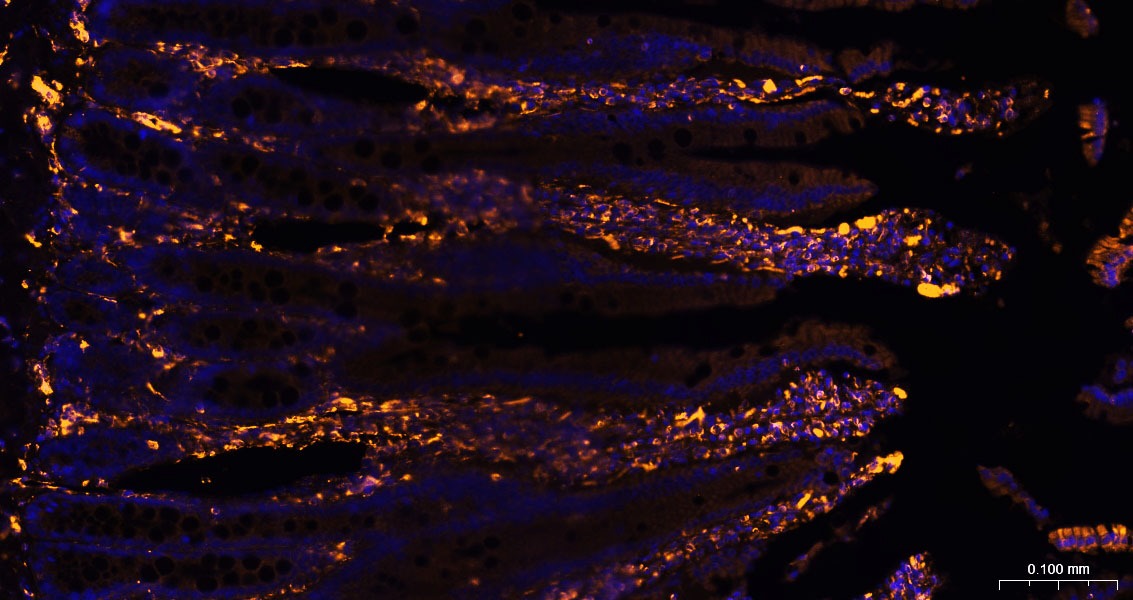

26. Paraformaldehyde-fixed, paraffin embedded Rat Small Intestine; Antigen retrieval by boiling in sodium citrate buffer (pH6.0) for 15 min; The section was incubated with Vimentin Polyclonal Antibody, Unconjugated (TMAB-01966) at 1:200 overnight at 4°C, followed by a conjugated Donkey Anti-Rabbit IgG antibody for 90 minutes, and DAPI for nucleus staining.

27. Paraformaldehyde-fixed, paraffin embedded Mouse Small Intestine; Antigen retrieval by boiling in sodium citrate buffer (pH6.0) for 15 min; The section was incubated with Vimentin Polyclonal Antibody, Unconjugated (TMAB-01966) at 1:200 overnight at 4°C, followed by a conjugated Donkey Anti-Rabbit IgG antibody for 90 minutes, and DAPI for nucleus staining.